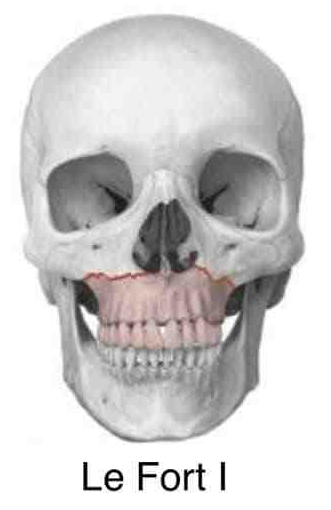

打在上颌骨上可能发生什么骨折呢?

第一型骨折(Lefort Ⅰ型骨折)其骨折线通过梨状孔下缘、上颌窦下部,横行到双侧上颌结节;

上颌骨Le Fort 骨折分型对临床诊治具有一定指导作用;除了共同临床表现之外,各型上颌骨Le Fort 骨折都具有其独特的临床表现,如:Le Fort Ⅱ型骨折会出现鼻及眶下缘的变形,常有鼻腔侧壁及上颌窦的损伤等,Le Fort Ⅲ型骨折则常形成颅面分离,使面中部凹陷、变长等;这些不同的临床表现对临床诊断有重要参考意义;各型上颌骨Le Fort 骨折在治疗上也具有一定特点,如Le Fort Ⅰ型骨折手术时多数只需采用口内前庭切口就能取得良好的疗效;而Le Fort Ⅱ、Ⅲ型骨折则多需口内前庭切口和头皮冠状切口联合应用才能获得满意的显露效果;再如Le Fort Ⅲ型骨折常伴有颅脑损伤和颅底骨折,处理时应注意颅脑损伤的诊治。